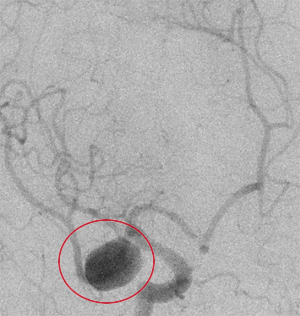

コイル塞栓手術前

コイル塞栓手術後